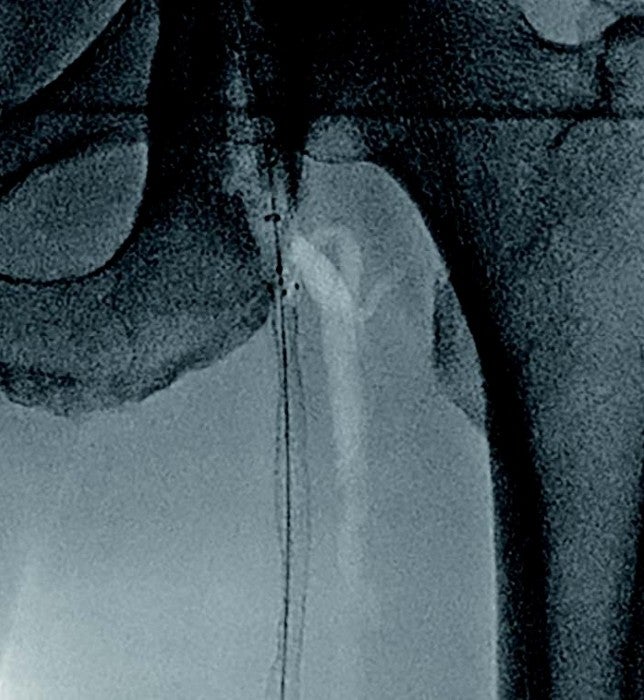

- 造影上は良好な血流改善を得られたが、IVUSではSFA起始部にプラーク残存を認めた(図3)。

- プラークをフルカバーするため、SFA起始部にバイアバーン® ステントグラフト径6.0/長50 mmを追加留置(図4)。

- 径6.0/長150 mm高圧バルーンにて高圧拡張を追加し、DFAの血流も問題がないことを確認して手技終了(図5)。